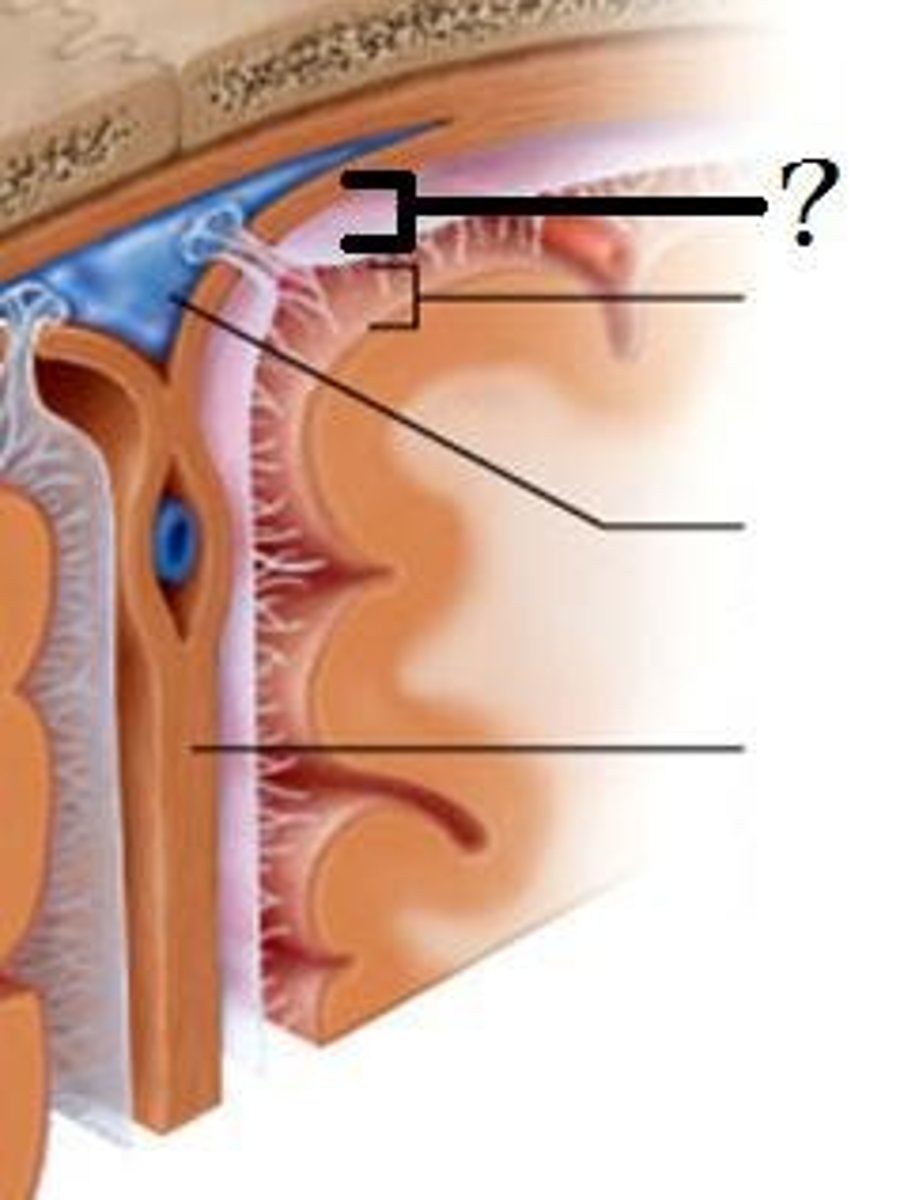

Meninges

-Three connective tissue membranes that envelope the CNS

-Protect the CNS and provide structural framework for its arteries and veins

Meninges Location

-Lies between the nervous tissue and bone

Cranial dura mater

-Outer periosteal

-Inner meningeal

-Folds inward to extend between parts of the brain

Cranial dura mater location

-Layers separated by dural sinuses

-Pressed closely against cranial bones

=No epidural space

=Only attached to bone around foramen magnum, stella turcica, crista galli, and sutures of the skull

Periosteal

-Equivalent to periosteum of cranial bones

Meningeal

-Continuous into vertebral canal and forms dural sheath around spinal cord

Dural sinuses

-Separates layers of cranial dura mater

Arachnoid mater

-Transparent membrane over brain surface

Subarachnoid space

-Separates arachnoid mater from pia mater below

Subdural space

-Separates arachnoid from dura mater above in some spaces

Pia mater

-Very thin membrane that follows contours of brain, even dipping into sulci

-Not usually visible without a microscope